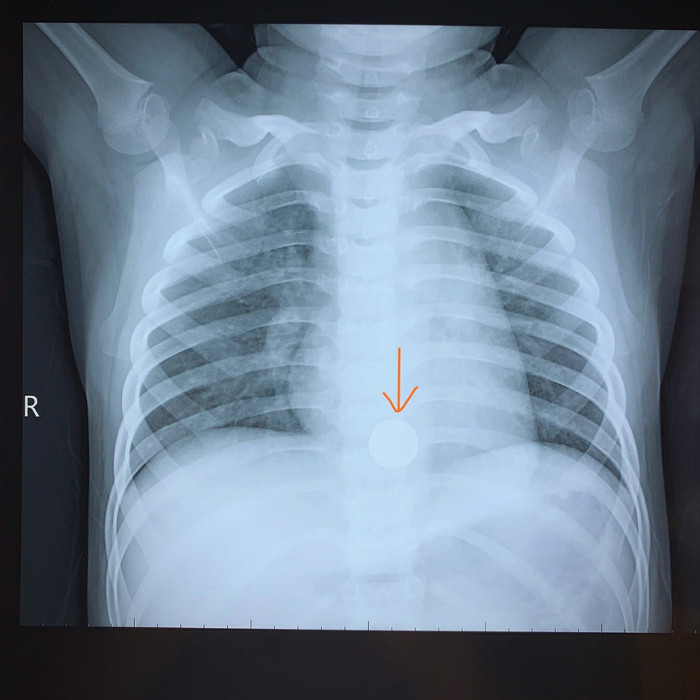

Dị vật pin cúc áo trong người bé trai 5 tuổi